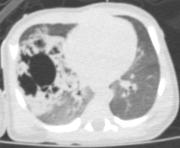

radiotrasparenza, attribuibile a un elemento dell'incubatore. Per una miglior definizione del problema, anche in vista dell'intervento, viene effettuata una TC-polmonare che evidenzia a destra una formazione irregolarmente ovalare di circa 5 cm di diametro massimo, apparentemente ben marginata, con numerose formazioni cistiche aerate circostanti (Figure 2 e Figura 3). Alla luce della diagnosi il bambino viene quindi sottoposto con successo ad intervento di lobectomia parziale dei lobi medio e superiore di destra. |

| Figure

2 a b. TC-polmonare: evidente a dx una formazione

irregolarmente ovalare di circa 5 cm di diametro massimo. | ||

| La

formazione � apparentemente ben marginata, con numerose

formazioni cistiche aerate circostanti. Il successivo decorso postoperatorio non ha presentato complicazioni (2 giorni di ventilazione meccanica e drenaggio pleurico). L'alimentazione gi� avviata con suzione autonoma prima dell'intervento, � stata ripresa il giorno successivo all'operazione con buona tolleranza ed il bambino � stato dimesso, a diciotto giorni di vita, in buone condizioni generali ed in allattamento materno esclusivo, con un programma di follow-up presso la chirurgia del nostro istituto. |